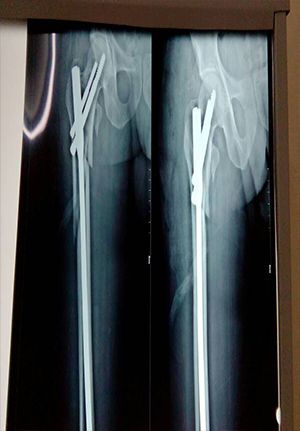

Proximal femoral nail for comminuated subtrochanteric fracture

Complex primary total hip replacment after failed internal fixation